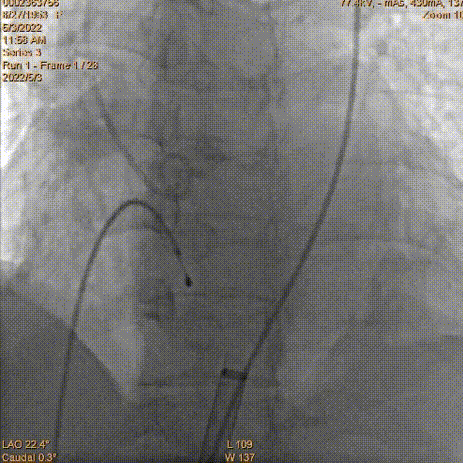

2.根据当前影像及测量数值,推荐·LAO·22·° ·CAU·0(右窦中心)左右跨瓣。

主动脉根部造影

导丝跨瓣

球囊预扩,左冠脉血流明显减慢,远端显影不清